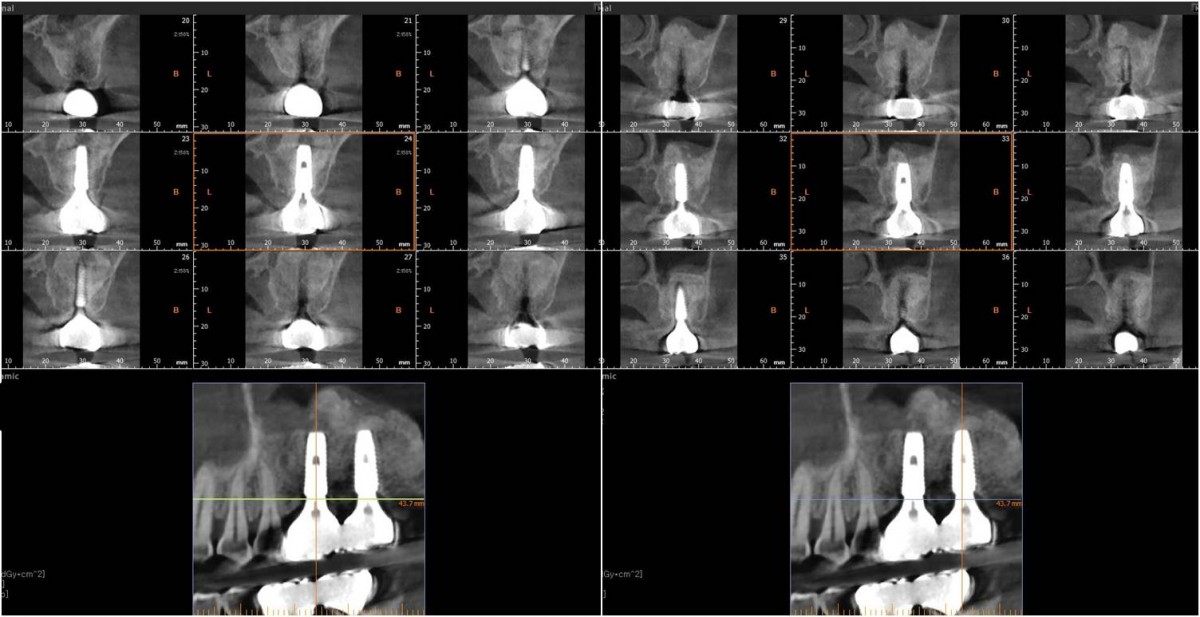

▲Panoramic radiograph after 1 year of the crown delivery.